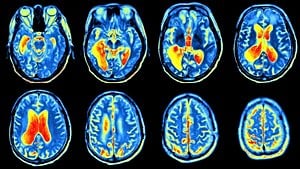

Tam olarak ne kadar radyasyon alınıyor?

Sadece PET'de alinan radyasyon miktari cok dusuk demek yerine karsilastirma yapmak iyi olabilirdi. Ornegin, tam olarak rakami hatirlamiyorum ama bir doktor, bir PET'den sonra 50 rontgen cektirmis gibi olursun demisti.